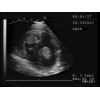

Thrombus libre (1 cm) dans l'oreillette gauche d' un chat atteint de cardiomyopathie hypertrophique

Durée. 0:20                 Dr Rocky Di Fruscia